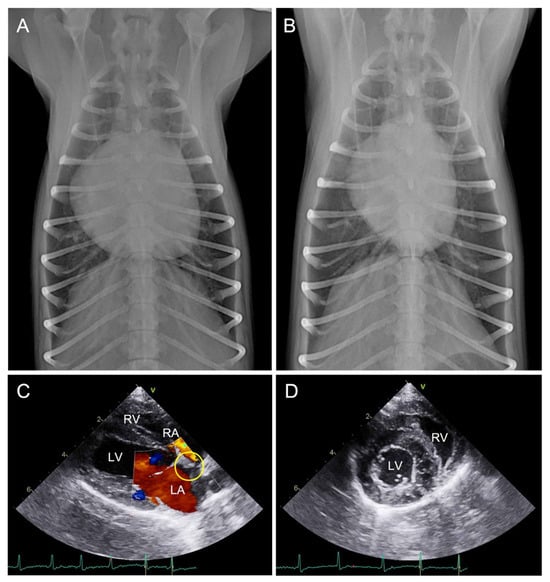

2. Case